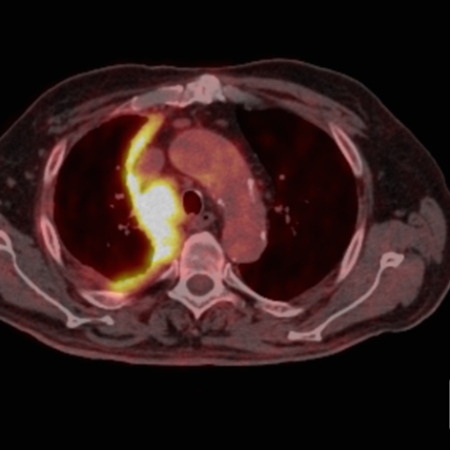

Au vu de toutes ces études, nous pensons que la sélection des patients, en particulier en utilisant en routine des biomarqueurs moléculaires et génomiques, l’imagerie avancée par TEP et scanner ou IRM thoracique, est fondamentale pour éviter des chirurgies lourdes et futiles. Les interventions chirurgicales devraient être réalisées uniquement par des chirurgiens thoraciques expérimentés dans des centres experts ayant un volume significatif et disposant d’unités de soins intensifs performantes, car les complications chirurgicales sont fréquentes et parfois graves. Les traitements systémiques par immunothérapie permettent d’obtenir des survies équivalentes au traitement multimodal chez les patients porteurs de mésothéliomes non-épithéliaux, et il semble donc logique de ne pas recommander de chirurgie de cytoréduction chez ces patients. Les patients porteurs de mésothéliomes épithélioïdes dont la tumeur semble extirpable en totalité devraient être adressés à un centre expert pour discussion en tumor board et évaluation.